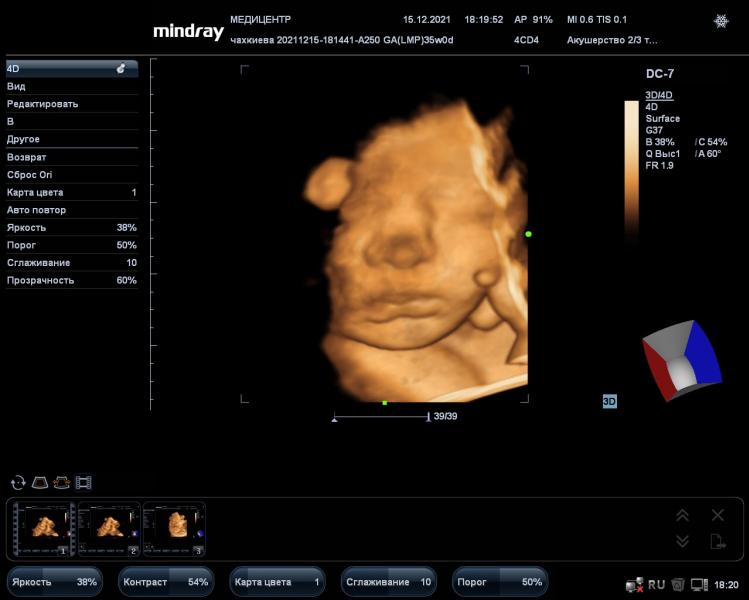

Девчонки, кто-нибудь делал 3д узи на 34-35 неделях? Как хорошо было видно малыша? Покидайте фотки, пожалуйста.

Я вот вчера сделала узи в медицентре, не особо понравилось качество фотографий. А в 4д вообще по 5 секунд 2 видео сделали(( Я думала весь процесс запишут на диск…

Итого за 2200 два коротеньких видео и 10 фото…